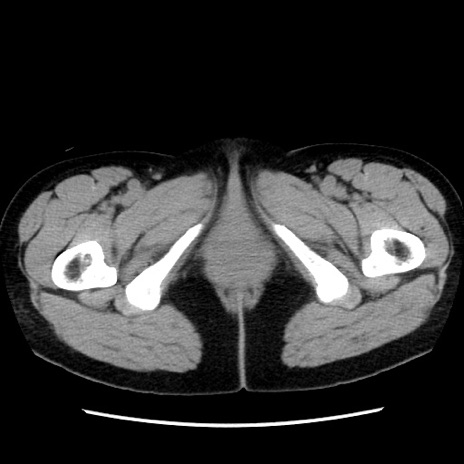

矢状断像

【症例】 50歳代女性

【主訴】 腹痛

【現病歴】前日生レバーを食べた。今朝に排便あり。 昼前に突然発症の腹痛を生じ、当院救急外来を受診した。

【既往歴】 子宮筋腫にてで子宮全摘後

【身体所見】 意識清明、腹部:平坦、軟、下腹部やや左を中心に圧痛・反跳痛あり、筋性防御あり

【データ】WBC 7800、CRP 0.07